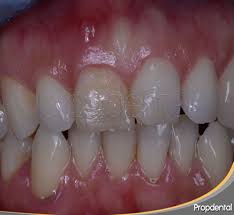

IMPORTANCIA DE LA GINGIVITIS

De la periodontitis, periodontosis, de la dentición difícil, de la formación de bolsas en encía, de la osteitis, etc., en el marco de un suceso focal dentógeno. Al respecto hay que decir lo siguiente:

La efectividad focal de estos cuadros clìnicos se basa primero en los mismos procesos inflamatorios crònicos y segundo en la reaccionabilidad vegetativa de la gigiva. Esta última "ratio" no se conocìa hasta el momento y sòlo ha podido ser aclarada gracias a las ùltimas investigaciones histològicas, electrónico-microscópicas e histo-químicas hechas por PLENK junior y RAAB (1969 1970) en nervios de la gingiva humana. Hemos comprobado allì por primera vez en la historia de la odontología científica la existencia de nervios adrenergos y autónomos (en la encia) lo que permite entender correlaciones funcionales de la misma con todo el organismo y a las que les faltaba el substrato morfològico.

La importancia clínica de este hallazgo se publicó por primera vez en 1970 (RAAB). La comprobación de que sí existen nervios vegetativos en la gingica es apropiada para explicar la hasta ahora oscurísima patofisiología de efectos a distancia "lanzados desde la gingiva" hacia todo el organismo y viceversa daños que le vienen a la gingiva proveniente de la mas variada y general gama de insultos patológicos de tipo tanto físico como psíquico (RAAB 1961). En la Universidad tenemos ya apabullantes estadísticas que le sirven de ejemplo a todo lo que estamos exponiendo.

El internista alemán M.L.Veil (1939) describió que en la mayoría de los casos con periodontosis las amigdalas se hallaban afectadas, o viceversa que una periodontosis severa y fétida solo lograba curarse después de una amigdalectomía. Se sabe además de casos en que existe una gingivitis crónica o aguda, pueden aparecer simultáneamente afecciones de caracter reumático en varias articulaciones, o molestias a distancia circunscritas a órganos. Este caso se da preferentemente en aquellos lugares del cuerpo cuya estructura heredada presenta constitucionalmente una clara debilidad de su sistema o también alrededor de sitios que sufrieron enfermedades años atrás. Sucede lo mismo con áreas cuya sobrecarga tisular es evidente por ejemplo: allí donde la estática del esqueleto está alterada. Todos estos factores crean en el cuerpo puntos de resistencia menor, mejor dicho puntos de reacción mayor, de tal modo que es allí donde anidan en primera linea irritaciones e interferencias.

Hasta ahora se venía culpando de todos estos sucesos focales que siempre acompañan, así como también a las alteraciones osteíticas. Sabemos que bajo la influencia de una situación hormonal de stress permanente como la pubertad, el climaterio y el embarazo o también un schock psíquico, como por ej: situaciones conflictivas en el trabajo y en la familia, puede presentarse una gingivitis sin que para ello podamos encontrar la culpabilidad de algún factor local. Las interpretaciones dadas a estos hechos reales no lograron satisfacernos núnca. Según nuestros conocimientos actuales sobre la morfología de la gingiva humana salta a la vista la explicación siguiente: La existencia de fibras vegetativas nerviosas de tipo adrenergico y autónomo en la encía humana, cosa hasta ahora desconocida, comprueba sin lugar a dudas que toda la estructura de sostenimiento y soporte del diente junto a su tejido conectivo elástico que le garantiza su función orgánica de cohexión y fortaleza, se somete a las regulaciones vegetativas de todo el organismo, a través de la interconexión que les facilita el tejido conectivo blando, rico en células y entretejido en toda la estructura elastica en unión con las citadas fibras nerviosas vegetativas y autónomas.

Este hecho le da capacidad para reaccionar y regular vegetativamente en forma indipendiente. En este reconocimiento fundamental está la importancia clínica de los resultados de nuestras investigaciones científicas. A esta circunstancia se debe también el que nosotros, a nivel academico, hayamos podido comprender y luego aceptar la patofisiología y la patogenesia de efectos a distancia desencadenados desde terrenos periodontales y asímismo las diversas patologías presentadas por la gingiva como provenientes de toda suerte de influencias externas e internas. Nuestras múltiples observaciones clínicas recibieron en base a los resultados de nuestras investigaciones científicas, por primera vez, la correspondiente corroboración morfológica.